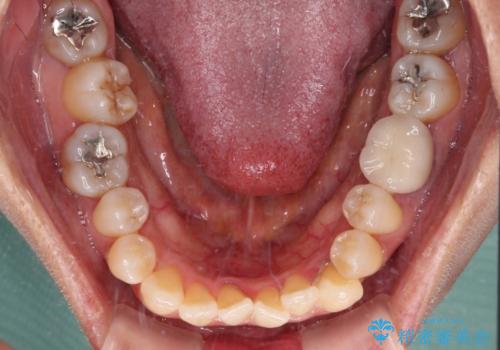

受け口と八重歯を改善 インビザライン矯正治療

- 前歯のデコボコや八重歯を治したいとのことで来院された患者様です。

受け口傾向の骨格であり、前歯はクロスバイトまたは切端咬合となっており、下顎を中心に歯列全体の後方移動を行い、IPR(歯と歯の間を削る)によってデコボコが解消するように設計し、インビザラインにより治療を行うこととしました。